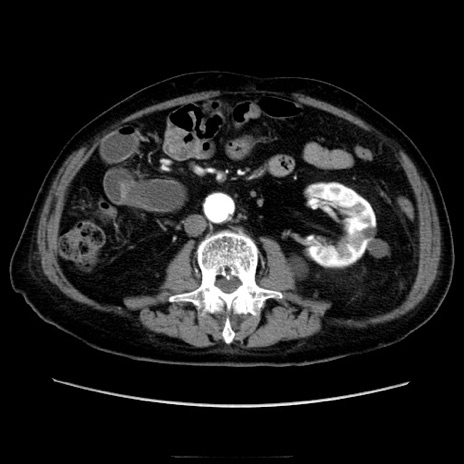

冠状断像

症例21(横断像)

【症例】70歳代男性

【主訴】腹痛

【現病歴】肝硬変・肝細胞癌にてかかりつけの方。約9時間前に食後より腹痛出現。症状が徐々に増悪し、嘔吐出現したため来院。

【既往歴】肝硬変、肝細胞癌(RFA、TACE後)

【身体所見】意識清明、表情苦悶様、BT 36℃、BP 129/78mmHg、P 88bpm、SpO2 97%(RA)、右上腹部から心窩部にかけて圧痛あり、反跳痛なし、筋性防御あり。

【データ】WBC 5800、CRP 0.16